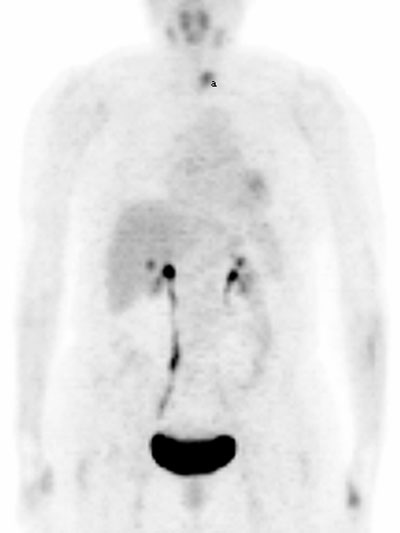

Fig. 7. - Imágenes coronal y lateral de tomografía por emisión de positrones de cuerpo completo. Chica de 17 años en estudio por sarcoma de fémur derecho. Se aprecia moderado aumento del metabolismo de la [18]FDG en mamas y en timo (a), así como en región genital (estaba en periodo menstrual). volver

1.7. Tiroides La captación existente de [18]FDG en la glándula tiroides, puede corresponderse a una variante de la normalidad (fig.7). Aunque también puede apreciarse en casos de patología benigna como la tiroiditis o enfermedad de Graves.

En el caso de apreciarse una captación focal, siempre es importante el valorar su posible malignidad. Un elevado grado de captación de la glándula tiroides, debe sugerirnos una posible malignidad.

Otro elemento a tener presente es la localización de la glándula tiroides, ya que cuando esta se encuentra desplazada (por ejemplo en bocio intratorácico), es muy sugestivo de la existencia de alguna patología (fig.8), a pesar de presentar un grado de metabolismo de la [18]FDG dentro de los parámetros de la normalidad[3 , 4 , 22 , 23 , 24] .